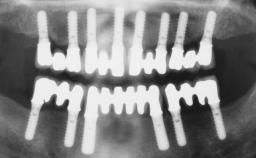

| Case Type | Extended Space |

| Jaw | Maxilla |

| Area | Anterior |

| # of Teeth | 4 |